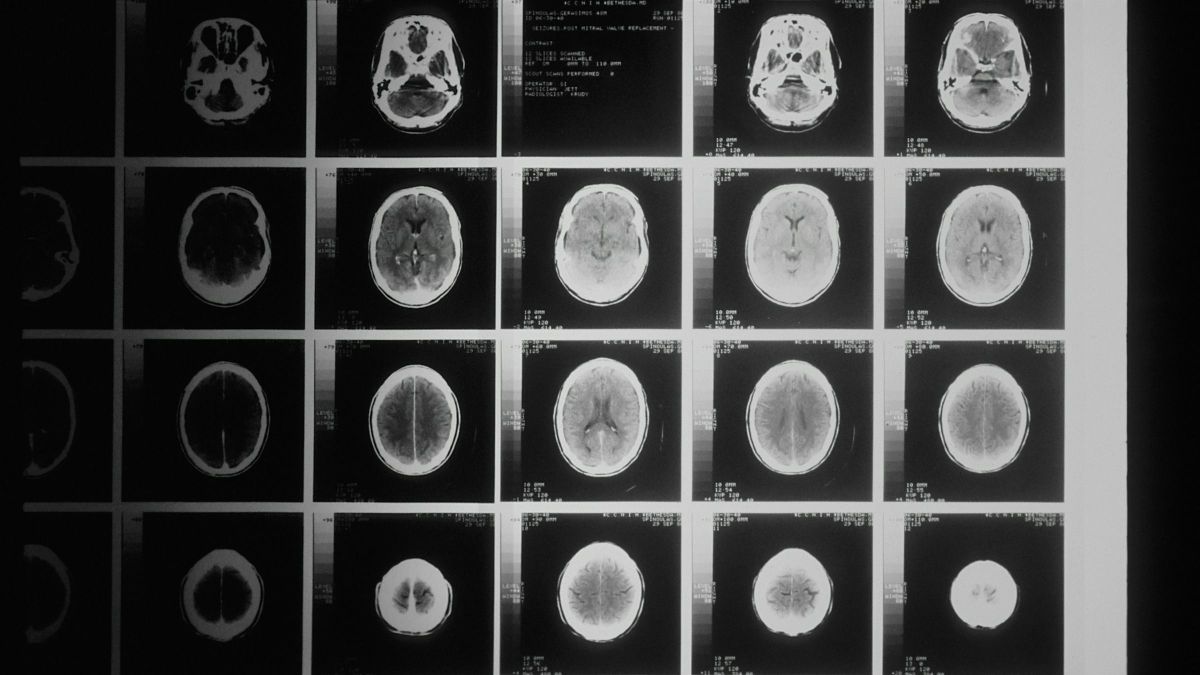

Valentina La Corte neurológus szerint a háttérben az agy bizonyos hálózatainak szokatlanul erős összekapcsolódása áll, különösen azoké, amelyek az emlékezésért és az önreflexióért felelősek.